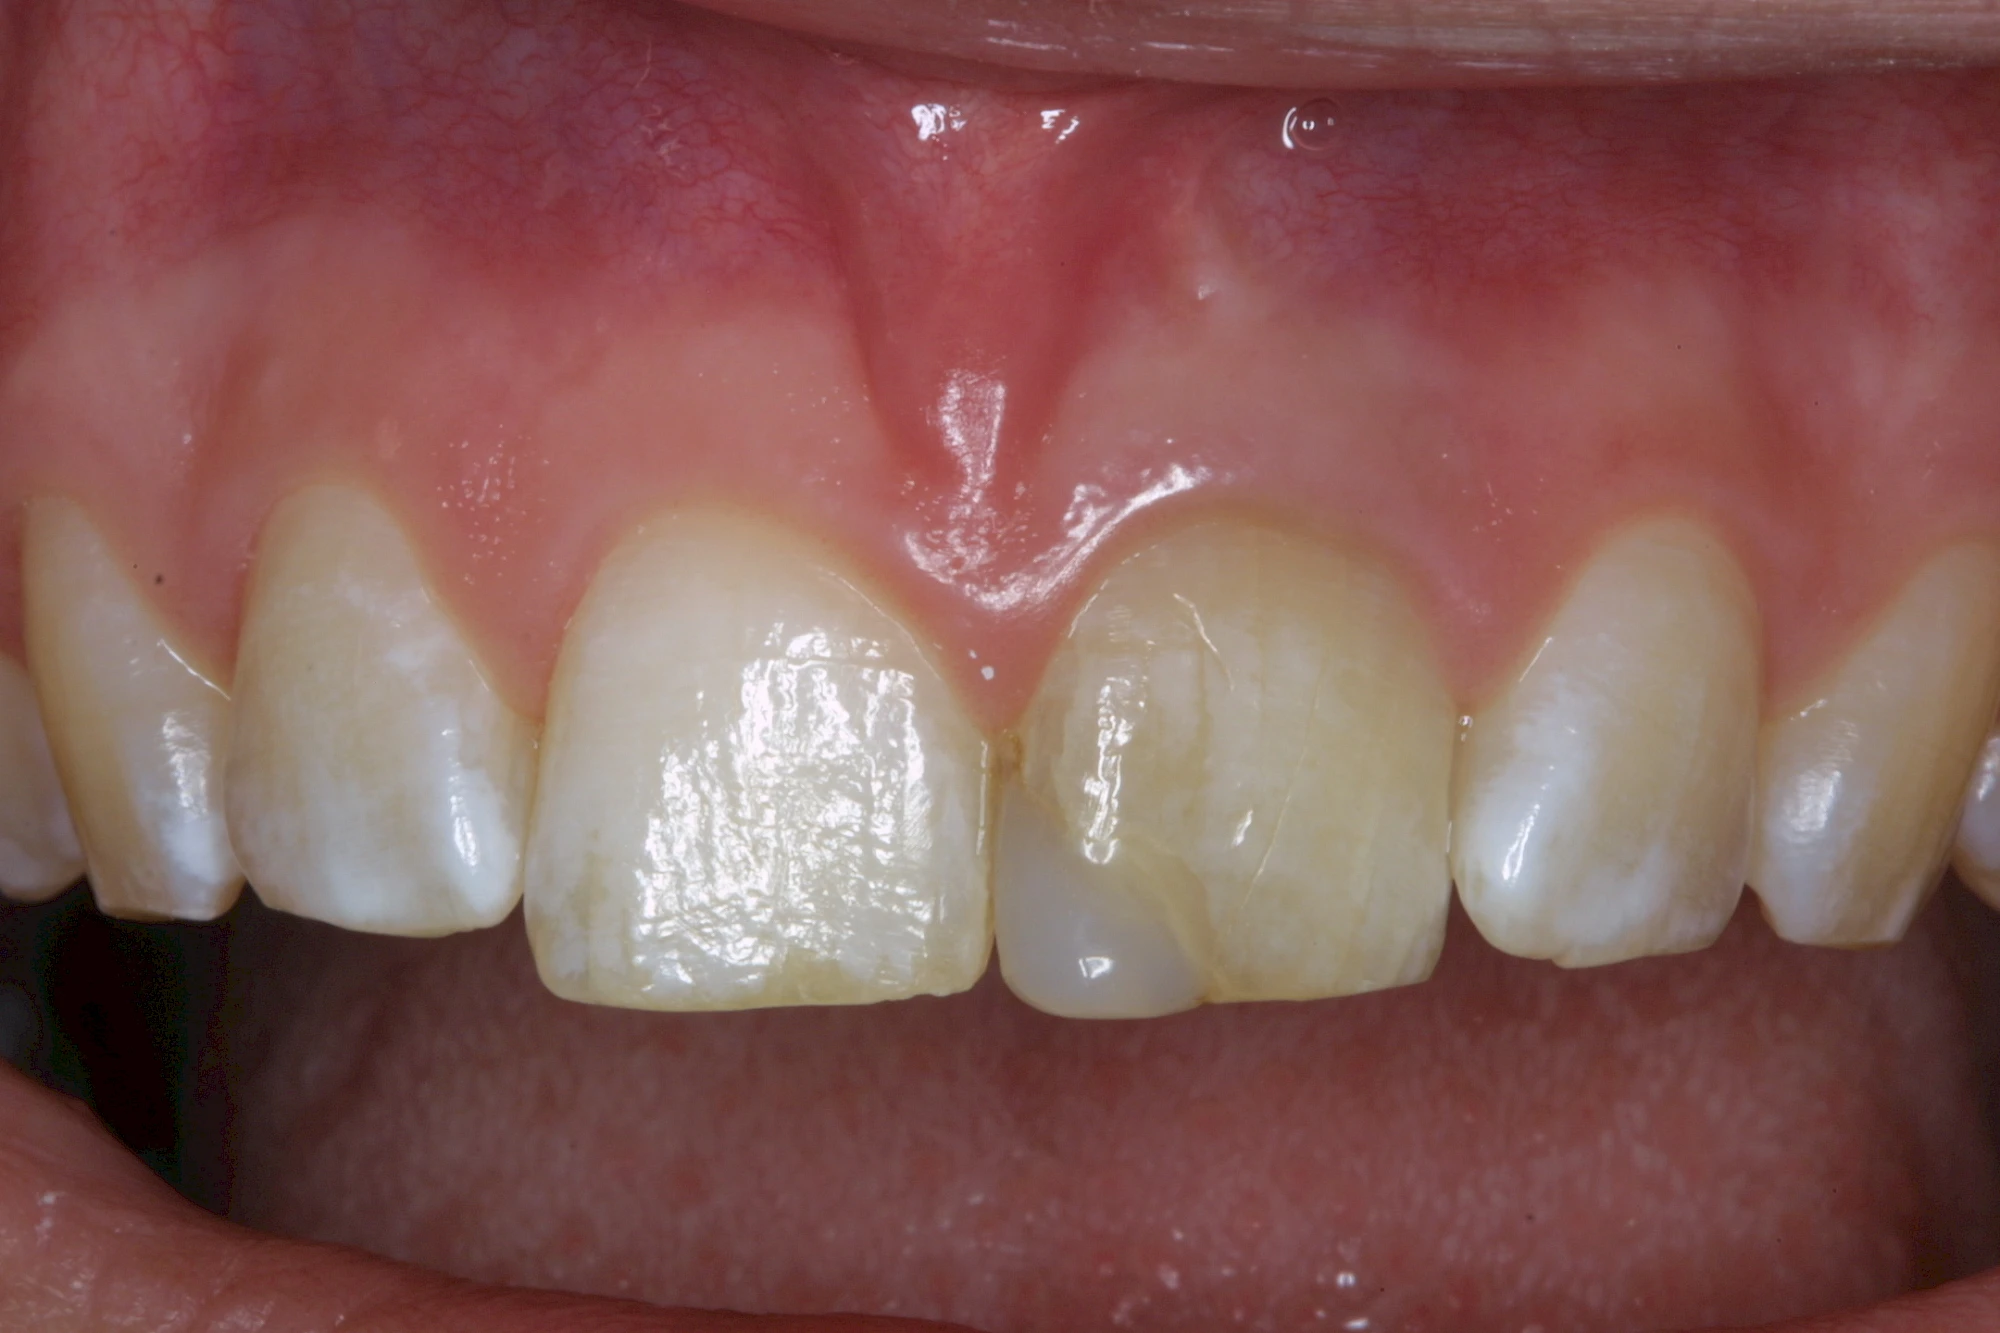

- Durch Blutabbauprodukte, weil der Zahnnerv abgestorben (einzelner Zahn, dunkel-flächig)

Ist ein einzelner Zahn deutlich dunkler als die Nachbarzähne kann das ein Zeichen sein, dass der Nerv abgestorben ist. Unter Umständen wurde bereits eine Wurzelkanalbehandlung vom Zahnarzt durchgeführt. Eine Abklärung durch den Zahnarzt ist in jedem Fall sinnvoll.